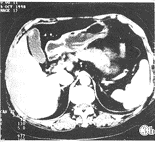

胆囊区呈低等混杂密度肿块,边缘模糊,略呈分叶状,胆囊腔消失或不规则缩小,增强后肿块不均匀强化,仍以低密度为主伴斑片状强化(图1)。本组有8例,占36.6%。

图1胆囊区呈低等混杂密度肿块,呈分叶,胆囊消失,并胆管结石。